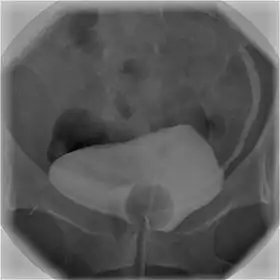

Cystography image showing contrast in the urinary bladder and left ureter (right side of image).

Using a urinary catheter, radiocontrast is instilled in the bladder, and X-ray imaging is performed. Cystography can be used to evaluate bladder cancer, vesicoureteral reflux, bladder polyps, and hydronephrosis. It requires less radiation than pelvic CT, although it is less sensitive and specific than MRI or CT. In adult cases, the patient is typically instructed to void three times, after which a post voiding image is obtained to see how much urine is left within the bladder (residual urine), which is useful to evaluate bladder contraction dysfunction. A final radiograph of the kidneys after the procedure is finished is performed to evaluate for occult vesicoureteral reflux that was not seen during the procedure itself.[1]